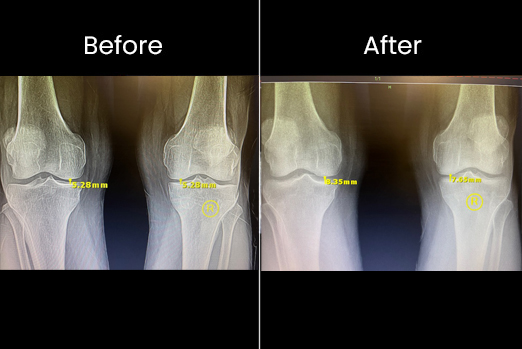

This patient was seen in our office with "constant right knee pain" left knee pain as well but not as constant and not as severe. An MRI was done, the diagnosis was torn right posterior meniscus. He was told he needed surgery on his torn meniscus. Not wanting to have a surgery if possible. He looked for other alternatives and found our office. We did a procedure with stem cells in both knees. Now he is pain free and back in the gym.

Avid walker presented to our office and was unable to walk more than 100Yards because of debilitating pain. Tried hyaluronic acid injections 3X with no relief. We did one procedure in our office and he is now walking any distance he wants "99% improvement". Small changes in joint tissue can make a huge difference in people's lives.